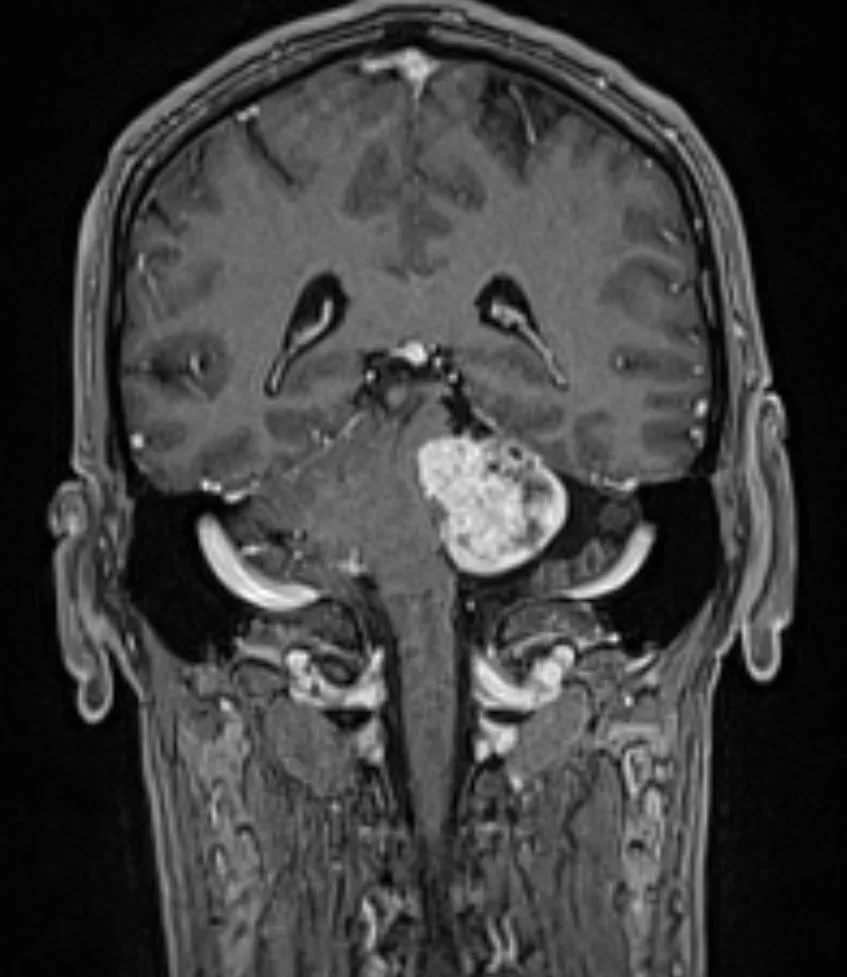

Ασθενής άνδρας, 52 ετών με κώφωση αριστερά και ιλιγγική συνδρομή.

Η μαγνητική τομογραφία εγκεφάλου ανέδειξε χωροκατακτητική εξεργασία στην αριστερή γεφυροπαρεγκεφαλιδική γωνία συμβατή με ακουστικό νευρίνωμα (αιθουσαίο σβάννωμα) και πίεση επί του στελέχους (Koos IV).